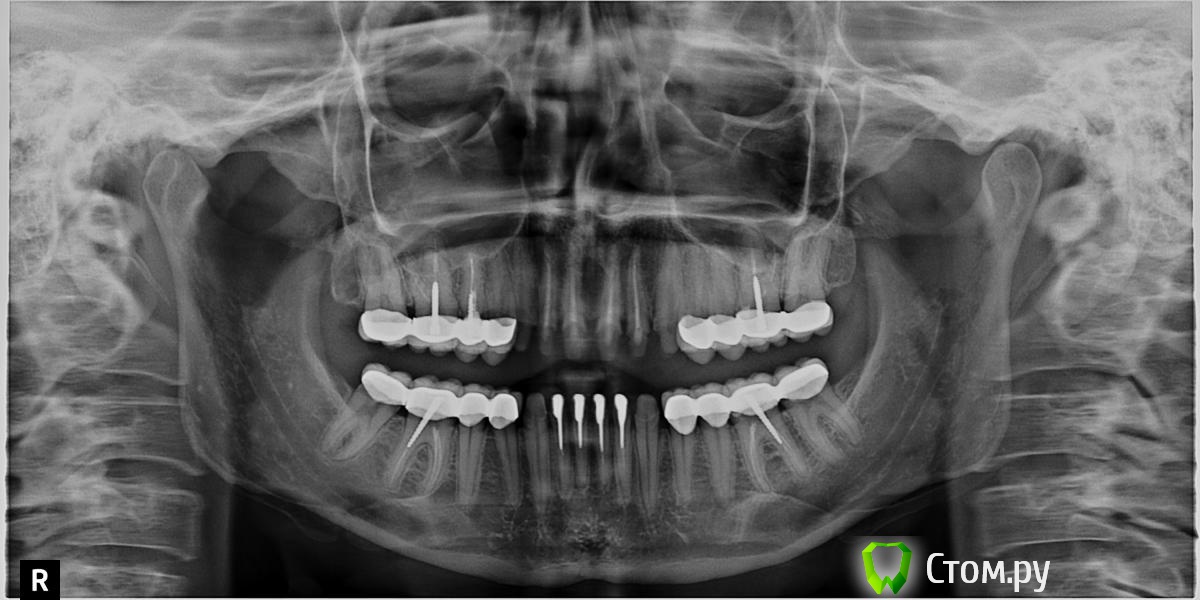

Juliafm Опубликовано 28 июля, 2014 Поделиться Опубликовано 28 июля, 2014 Добрый день! Вопрос по прделанной работе. Оцените,поож-та, качество пломбировки каналов и прилегание коронок , удалены нервы в передних 4 верхних и нижних зубах - стоят временные коронки. Также удалены и некоторые нервы в боковых зубах - стоят коронки м/к. Врач ,который проводил работу утверждает что сделано все правильно, другие врачи критикуют работу, в том числе и качество пролечивание каналов. Ссылка на комментарий

dr-krasnov Опубликовано 28 июля, 2014 Поделиться Опубликовано 28 июля, 2014 По панорамному снимку качество пломбировки зубов оценивать некорректно. Возможна масса допущений и разрешение не достаточно хорошее. Обычно для этого используются прицельные снимки. Попробуйте их достать и показать нам. 1 Ссылка на комментарий

Bier Опубликовано 28 июля, 2014 Поделиться Опубликовано 28 июля, 2014 Ну в нижних передних зубах каналы вообще пустые, верхние -лучше бы прицельные снимки увидеть Ссылка на комментарий

Mane Опубликовано 28 июля, 2014 Поделиться Опубликовано 28 июля, 2014 правильно что критикуют 1 Ссылка на комментарий